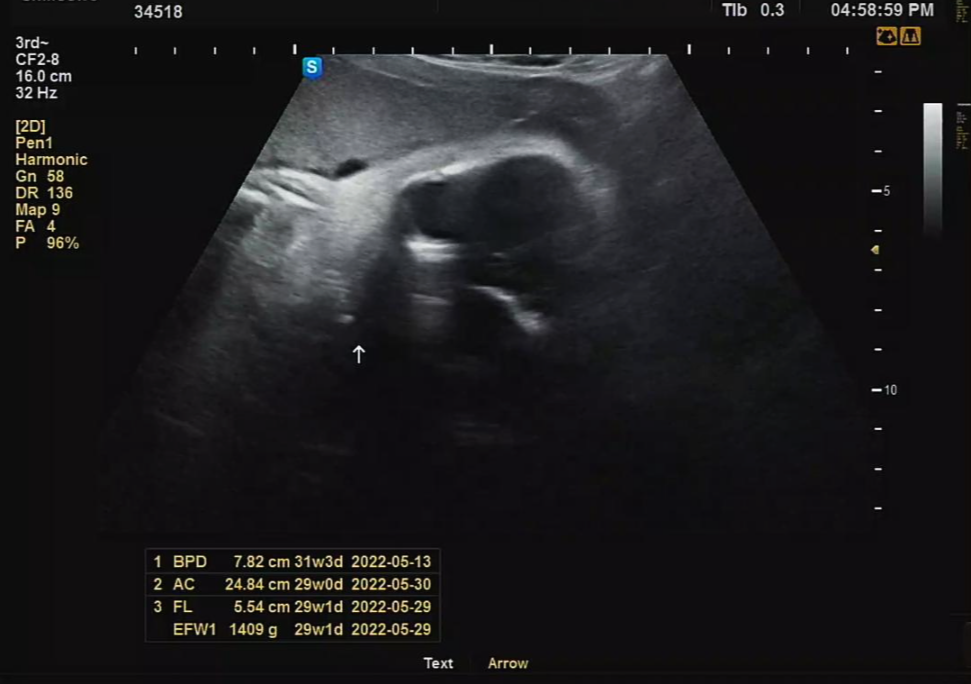

이번 주수에도 역시나 30주 기준 평균 주수에 비해 머리둘레는 살짝 크고, 배 둘레, 다리뼈가 한주 정도 짧게 나왔다. 흑흑 조금 마음이 아프긴 하지만 어쨌든 엄마 뱃속에 있는 상태라 크는 거와 상관없을 거라 생각된다.ㅎㅎ 다행히 체중은 1.4kg 때로 저번보다 살짝 적었던 체중인데 주수 대비 적절하게 나온 편이다.

별로 체크할 사항이 없어서 초음파 사진도 달랑 2장 밖에 안 해주셨다ㅜㅜ.. 앞으로도 이런 식으로 짧고 굵은 초음파 검사를 받을 듯싶다. 체중, 심박수, 머리둘레, 다리 길이 등만 체크하기 위함.

그래도 초음파 검사 중간에 까꿍이가 눈 뜨는 것을 원장님께서 순간포착하여 찍어주셔서 사진으로 남길 수 있었다. 손으로 얼굴 가리고 있어서 속상했는데 잠시나마 엄마, 아빠 기쁘게 해 줘서 고마워🧡💖